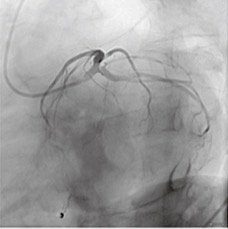

Clinical Images